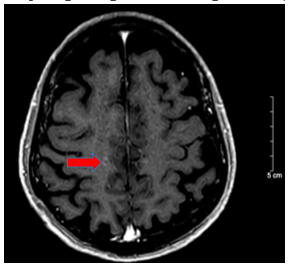

- Chụp cộng hưởng từ sọ não tháng 10/2024 (trước điều trị)

Hình 2:

Vỏ não thùy trán hai bên và thùy đỉnh phải có các nốt tăng ngấm thuốc sau tiêm, nốt lớn nhất ~ 4mm (mũi tên đỏ) – Theo dõi thứ phát

+ Chụp MRI sọ não sau điều trị:

Hình 8: So sánh phi chụp cộng hưởng từ sọ não trước điều trị có nốt tăng ngấm thuốc sau tiêm vùng vỏ não thùy trán thùy đỉnh phải ~ 3mm (mũi tên đỏ) của phim chụp trước điều trị. Hiện tại chụp lại phim MRI não đã không còn phát hiện các nốt ngấm thuốc bất thường.